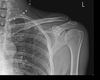

• Pedro404

Na to z tý druhý fotky ti dali jenom ortézu? To bych si nechal operovat, už jenom pro lepší pocit, že to nesrůstá nakřivo (i když by to pravděpodobně bylo bez omezení funkce) a rychlejší funkčnost. Tu ortézu máš aspoň na měsíc, ne?

• michal56

ta druha fotka je podruhe zlomene,chtel jsem to puvodne nechat operativne zpravit,ale 3 doktori mi to vymluvili tak nevim no,snad to sroste jak ma ,je to sice nakřivo,ale rikali ze to sroste.